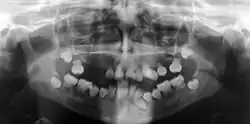

Preoperative panoramic radiographs showing features of dentin dysplasia type I | |

Dentin dysplasia (DD) is a rare genetic developmental disorder affecting dentine production of the teeth, commonly exhibiting an autosomal dominant inheritance that causes malformation of the root. It affects both primary and permanent dentitions in approximately 1 in every 100,000 patients.[1] It is characterized by the presence of normal enamel but atypical dentin with abnormal pulpal morphology. Witkop[1] in 1972 classified DD into two types which are Type I (DD-1) is the radicular type, and type II (DD-2) is the coronal type. DD-1 has been further divided into 4 different subtypes (DD-1a,1b,1c,1d) based on the radiographic features.[2]

In other words, affected primary teeth usually have abnormal -shaped or shorter than normal roots. “Crescent/half-moon shaped” pulp chamber remnant in permanent teeth can be seen on x-rays. The roots may appear to be darker or radiolucent/pointy and short with apical constriction. Dentine is laid down abnormally and causes excessive growth within the pulp chamber. This will reduce the pulp space and eventually cause incomplete and total pulp chamber obliteration in permanent teeth.[12][13] Sometimes periapical pathology or cysts can be seen around the root apex.[11] Most cases of DD associated with peri-apical radiolucency/ pathology have been diagnosed as radicular cysts, but some of them have been as diagnosed peri-apical granuloma instead.[14]